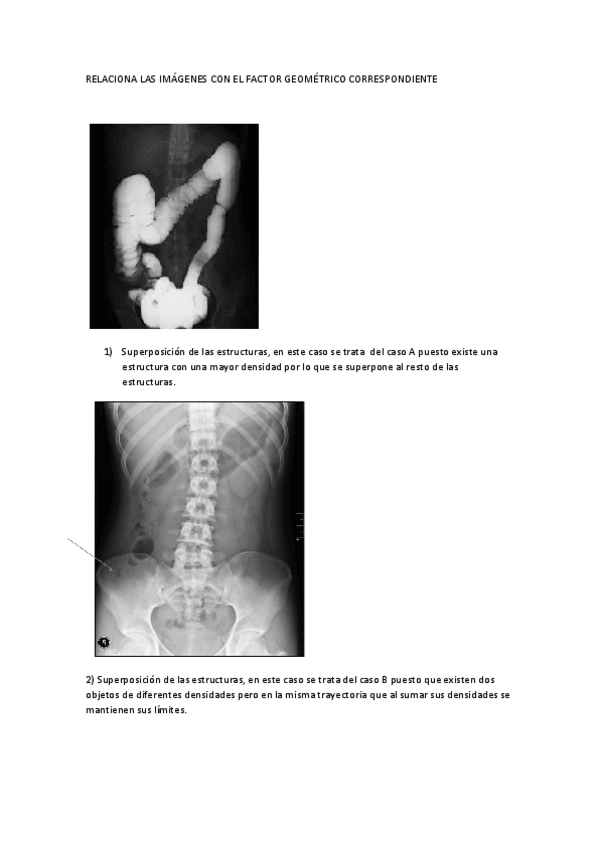

He publicado nuevos apuntes de Fundamentos Físicos y Equipos: Informacion-adicional-GEOMETRIA-DE-LA-IMAGEN.pdf

He publicado nuevos apuntes de Fundamentos Físicos y Equipos: EJERCICIO-GEOMETRIA.pdf